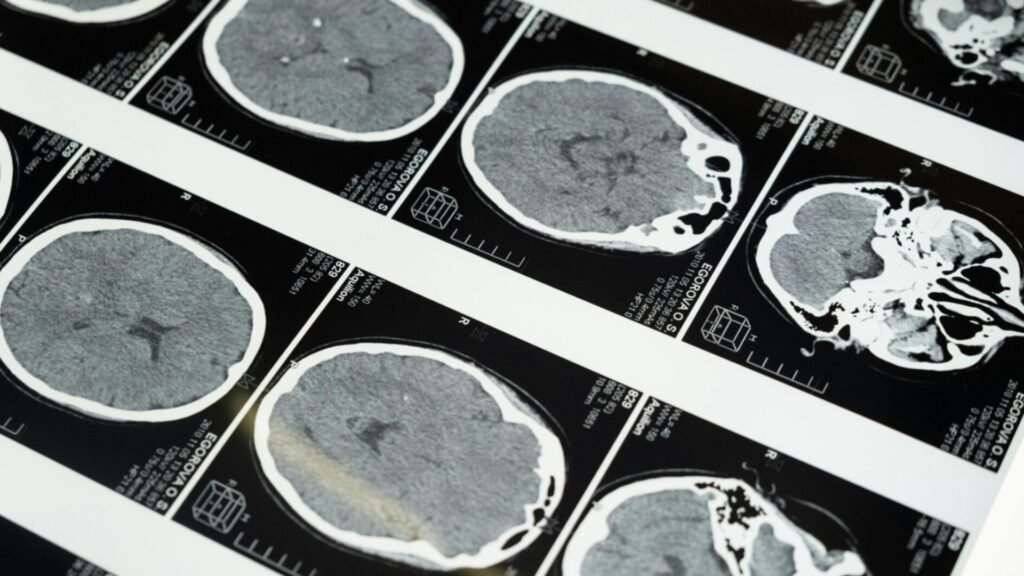

A Universidade Federal do Paraná (UFPR) tem intensificado pesquisas e ações voltadas à prevenção e ao tratamento do Acidente Vascular Cerebral (AVC). O aumento de casos, especialmente entre jovens, reforça a importância dos estudos realizados pela instituição em diferentes áreas da saúde.